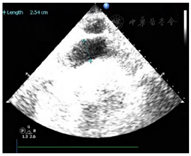

患者,女性,84岁,因"反复胸痛1周,持续加重8 h"于2021年8月17日急诊收治入院。既往无高血压、糖尿病病史。入院查体:血压105/56 mmHg(1 mmHg=0.133 kPa),神清,气略促,对答切题,颈软,颈静脉无怒张,双肺呼吸音粗可闻及较多的湿啰音,心率112次/min,律齐,各瓣膜区未闻及病理性杂音,腹平软,无压痛,反跳痛,肝脾肋下未及。双下肢轻度浮肿,四肢肌力正常,病理征(-);急诊心电图示:急性广泛前壁心肌梗死(图1);胸部CT提示双侧间质性肺水肿可能(图2);实验室检查:肌钙蛋白T:3.13 μg/L,肌酸激酶同工酶:188.93 μg/L,D二聚体:1.36 mg/L。根据患者病史、心电图及心肌酶学明确诊断为急性ST抬高型心肌梗死,予以术前嚼服负荷量绿色通道行急诊再灌注治疗,冠脉造影示:前降支次全闭塞,远端TIMI血流0级,回旋支近端40%~50%局限性狭窄,TIMI血流3级,右冠起源左冠窦,无狭窄,TIMI血流3级,于前降支近端植入3.0 mm×18 mm Firebird 2支架一枚(附件冠脉造影+PCI图3、视频1)后安返CCU。继续予以心电及血流动力学监测,动态监测心电图及酶学改变,阿司匹林、替格瑞洛抗血小板聚集,他汀调脂、稳定斑块,扩管利尿改善心功能等治疗。3 h后患者突发血压下降为60/40 mmHg,四肢湿冷,动脉搏动弱,意识尚清,指末氧饱和度95%,心电监测提示窦性心动过速,心率130次/min。立即予以平衡液扩容,多巴胺+去甲肾上腺素提升血压,留置颈内静脉置管监测CVP,股动脉置管监测有创动脉压。床旁心超提示微量心包积液,右房室内径偏小(37 mm×18 mm,40 mm×22 mm),左室壁多壁段运动异常,EF35%(图4),床位医师考虑容量不足,继续补液扩容及血管活性药物升压,但患者血压仍未见回升;再次复查心超提示心包积液较前明显增多,未见室壁不连续及异常血流信号,考虑心包填塞(图5),立即行心超定位剑突下心包穿刺,引流出暗红色不凝血,予以心包置管留置引流出血性液体300 ml,患者血压恢复至119/49 mmHg,心率95次/min,再次复查心超示左室心尖处见几束细丝状异常血流信号局限于纤维膜状回声内,考虑左室心尖破裂伴假性室壁瘤可能性大(图6)

根据以上3条可以明确诊断为急性ST抬高型前壁心肌梗死,患者冠脉造影亦证实本诊断成立。患者查体无休克征象,入院血压105/56 mmHg,双肺较多湿罗音,胸部CT提示双侧间质性肺水肿可能,故按Killip分级为Ⅲ级。